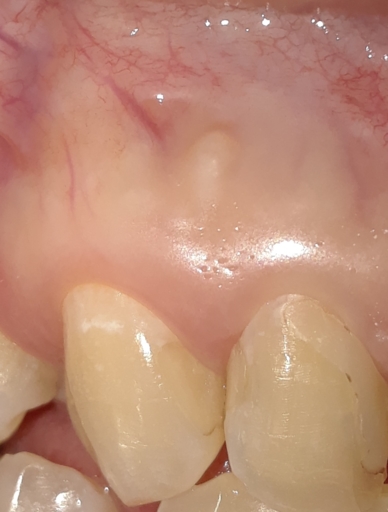

Hello! I found you on ask a dentist and I’m hoping you can ease a worried mind. I had a root canal on tooth 12 the beginning of February. Apparently the tooth had a tiny old filling that leaked. No infection but tooth was dying. Following root canal I had extreme pain. RC was redone in March, pain continued. This past Friday the Endodontist performed an Apicoectomy. There was small infection above the tooth root and some swelling. I am healing well. Main source of ache is in my chipmunk cheeks. Gums are tender but feel good. No swelling like there was about tooth root any longer. my question is, is it normal for the Apico tooth to feel different right now? Even a bit tender to pressure? It’s not necessarily painful but a definite “feeling” and tender. I thought that if the tooth had no root it would no longer feel sensation. Just sitting here worrying about this poor tooth and hoping someone has some thoughts on this. And I need to stop “testing” it! Thank you so much! I’m so insanely worried about this little tooth.